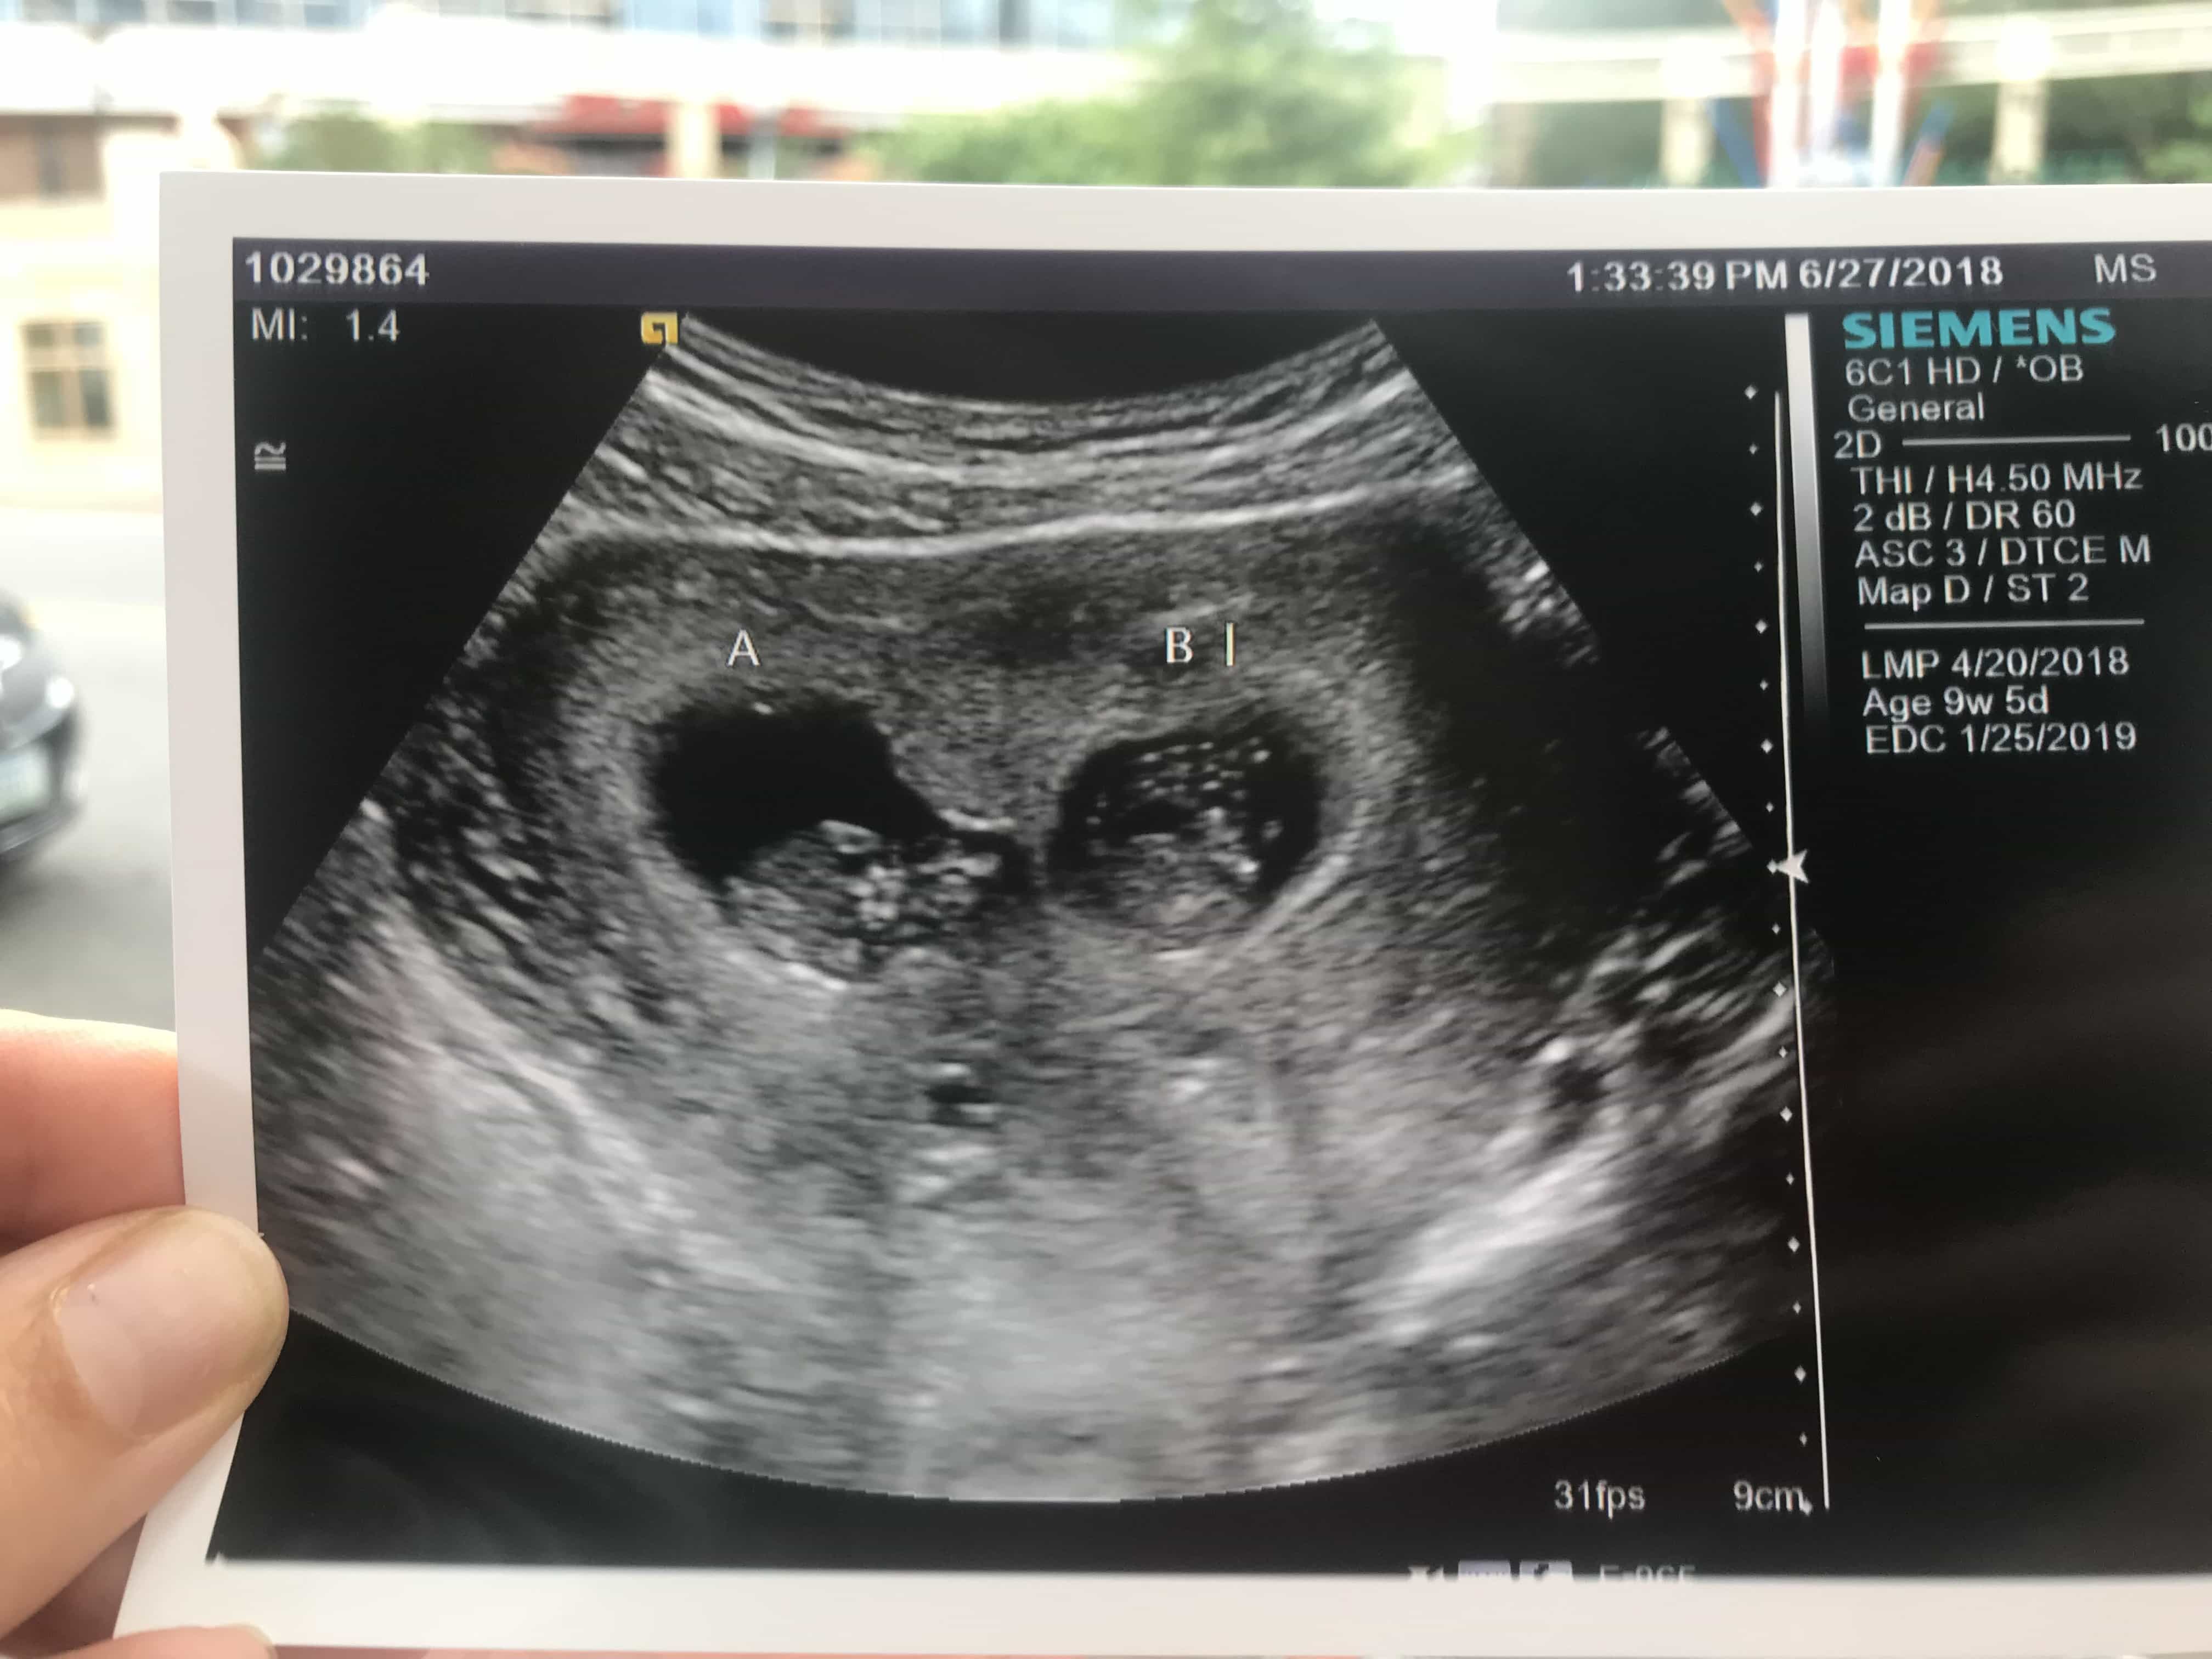

- Ultrasound Photos of 9 Weeks Pregnant With Twins

Ultrasound Photos of 9 Weeks Pregnant With Twins